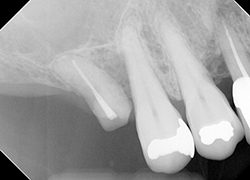

【治療後】

無事引き起こすことが出来ました。治療期間は約2ヶ月です。

後戻りを防ぐため、仮歯で一定期間様子を見つつ、最終補綴物を入れることが出来、現在も良好に使用されています。

【一般的なリスクや副作用】3根中の1根のみの残存だったので、どれぐらい持つか不安要素もありましたが、もう10年以上経過していますが動揺等も見られず健康に機能しています。